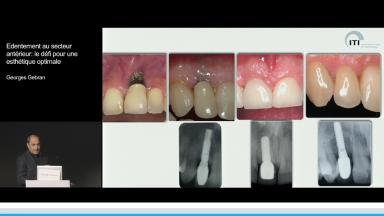

Edentement au secteur anterieur: le défi pour une esthetique optimale

A partir de la description des facteurs de risque esthétique du bloc incisivo-canin maxillaire, de la présence d’os et de gencive autour des implants, le conférencier présente une succession de cas cliniques décrivant ses procédures chirurgicales et prothétiques.

- de déterminer le bon timing de chirurgie implantaire post extractionnelle

- de réfléchir sur la préservation à moyen-long terme de l’os autour des implants